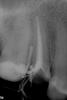

Ashley Опубликовано 20 мая, 2010 Автор Поделиться Опубликовано 20 мая, 2010 (изменено) при соблюдении толщИн ничего не ломается.если врач сможет расширить корень под стекловолокно (т.е. будет достаточный запас тканей корня по толщине) - то и вкладка не из металла будет уместна. По прочности и прогнозу - даже лучше, чем стекловолокно.а о каком зубе речь? есть снимок? если да - выкладывайте Может, врач просто не умеет делать такие вкв? Хотя коронка будет из оксида. Буду еще спрашивать его по поводу неметаллич. вкв. Вот снимок зуба - 5 верхний зуб, я о нем уже писала в другой теме, зуб нужно будет перелечивать. Изменено 20 мая, 2010 пользователем Ashley Ссылка на комментарий